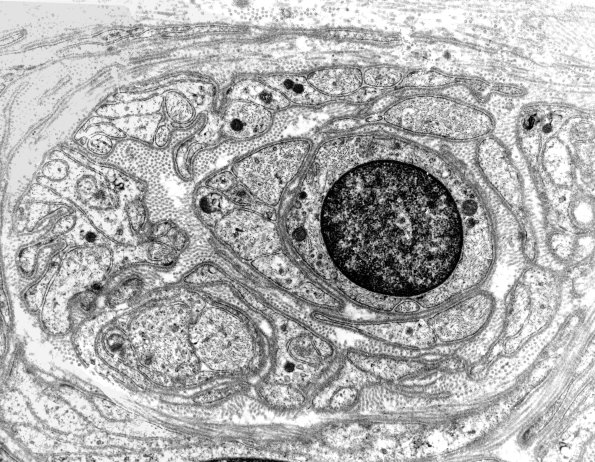

A small POB with a central collection of Schwann cell processes. (electron micrographs)